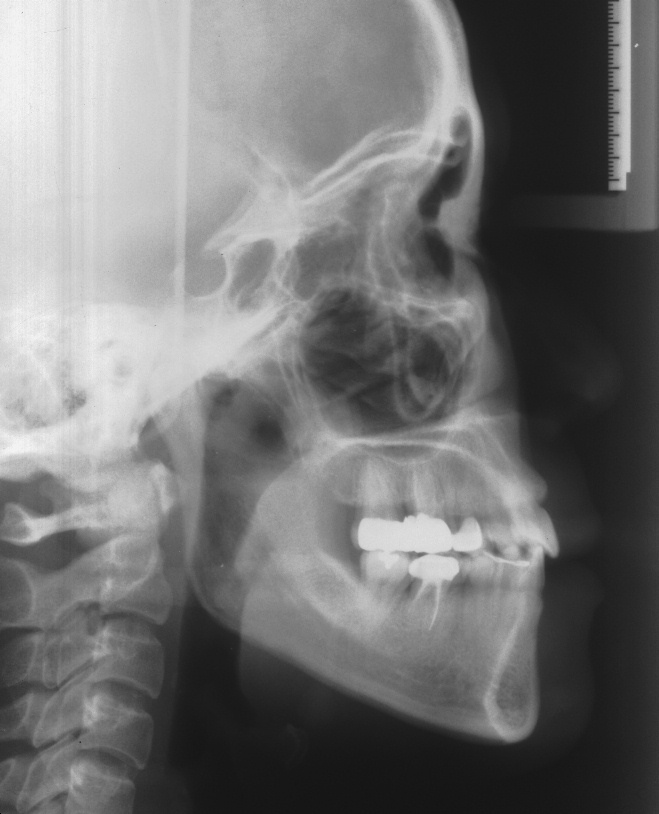

치료 전 사진입니다.